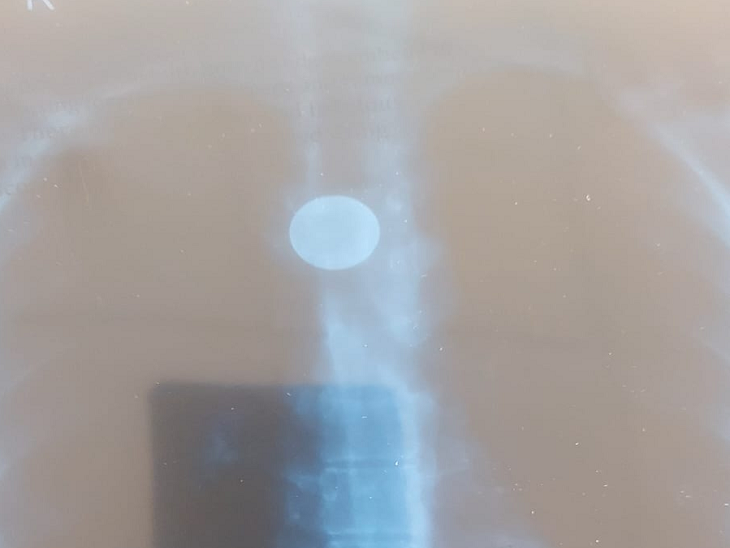

AIMS चमियाणा में एंडोस्कोपी के दौरान नजर आ रहा सिक्का।

लड़की की फूड पाइप में गोल आकार का नजर आ रहा सिक्का।

शिमला के चमियाना स्थित AIMS सुपर स्पेशियलिटी अस्पताल के डॉक्टरों ने एक बड़ी उपलब्धि हासिल की है। गैस्ट्रोएंट्रोलॉजी विभाग की टीम ने 15 साल पहले एक लड़की द्वारा निगला सिक्का आज (शुक्रवार को) सफलतापूर्वक बाहर निकाल दिया है।

लड़की की उम्र 23 साल बताई जा रही है। जब वह दूसरी कक्षा में पढ़ती थी, तब उसने यह सिक्का निगल दिया था। छोटी उम्र में लड़की ने मुंह में सिक्का डाला और गलती से निगल गई, जिससे सिक्का फूड पाइप में फंस गया।